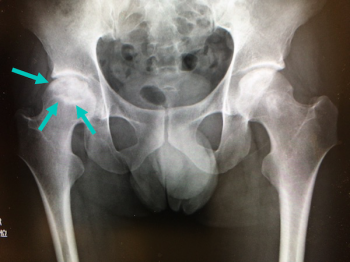

今日、ご紹介するのは、大腿骨の病気 特発性大腿骨頭無腐性壊死についてご紹介していきます。

特発性大腿骨頭無腐性壊死とは

成人の大腿骨頭に明らかな原因がなく、血流の低下により壊死(血が通わなくなって骨組織が死んだ状態)に陥った状態です。

中年の男性に多く、片側に発症するが、数年で70%くらいが両側性になる。

特発性大腿骨頭無腐性壊死の検査・診断・治療

検査・診断

X線、CTスキャン、磁気共鳴画像法(MRI): 骨の変化